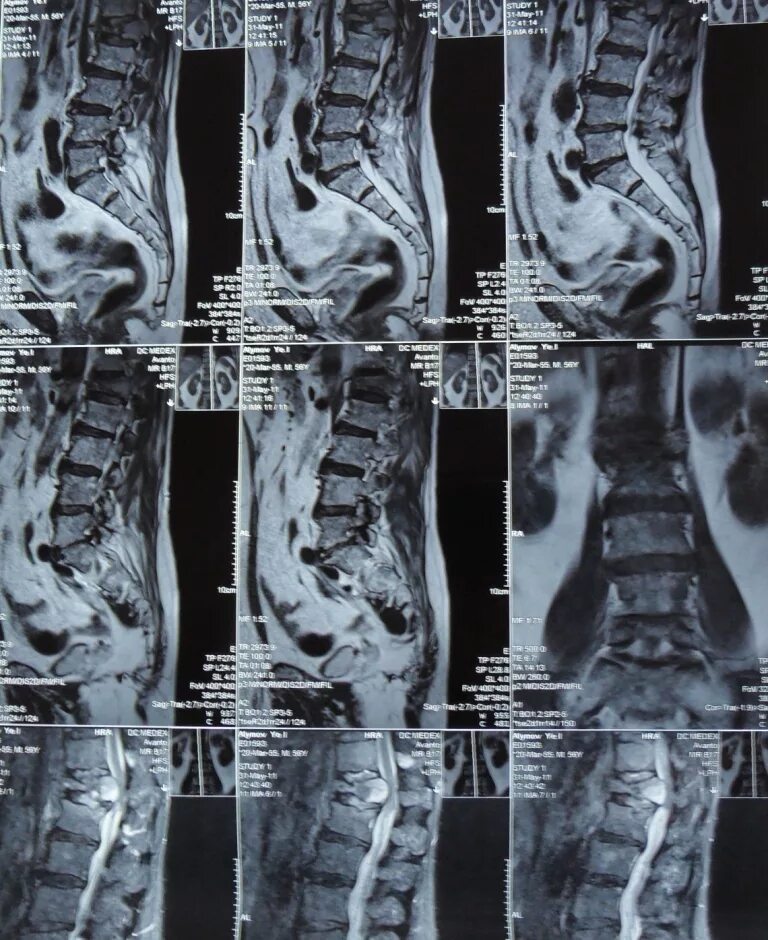

4 стадия метастазы позвоночника